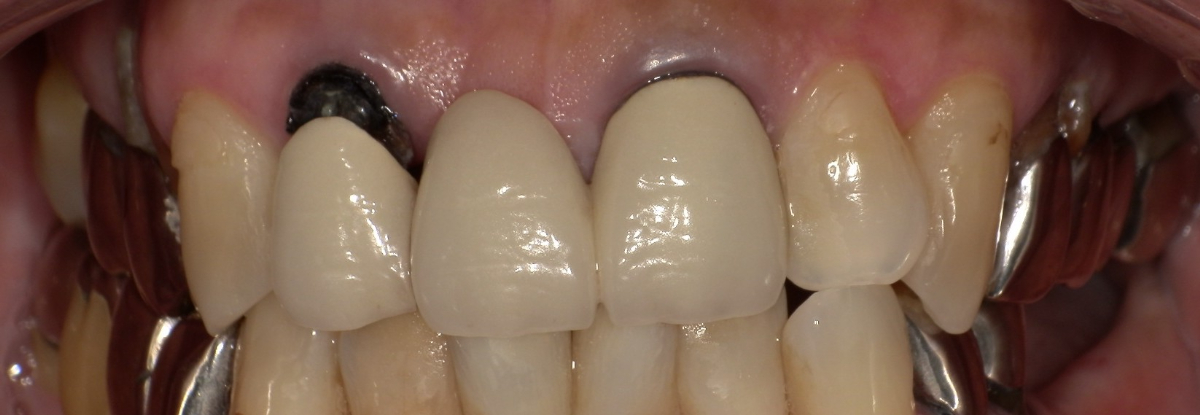

<治療前>

<治療後>

主訴:下の銀歯をセラミックに変えたい

上部構造:全てフルジルコニア

費用:¥524,000

治療期間:2ヶ月

副作用・リスク:銀歯のみ変更できる場合もありますが、歯の状態により根の治療やう蝕治療、歯周病の治療が必要になる場合があります。